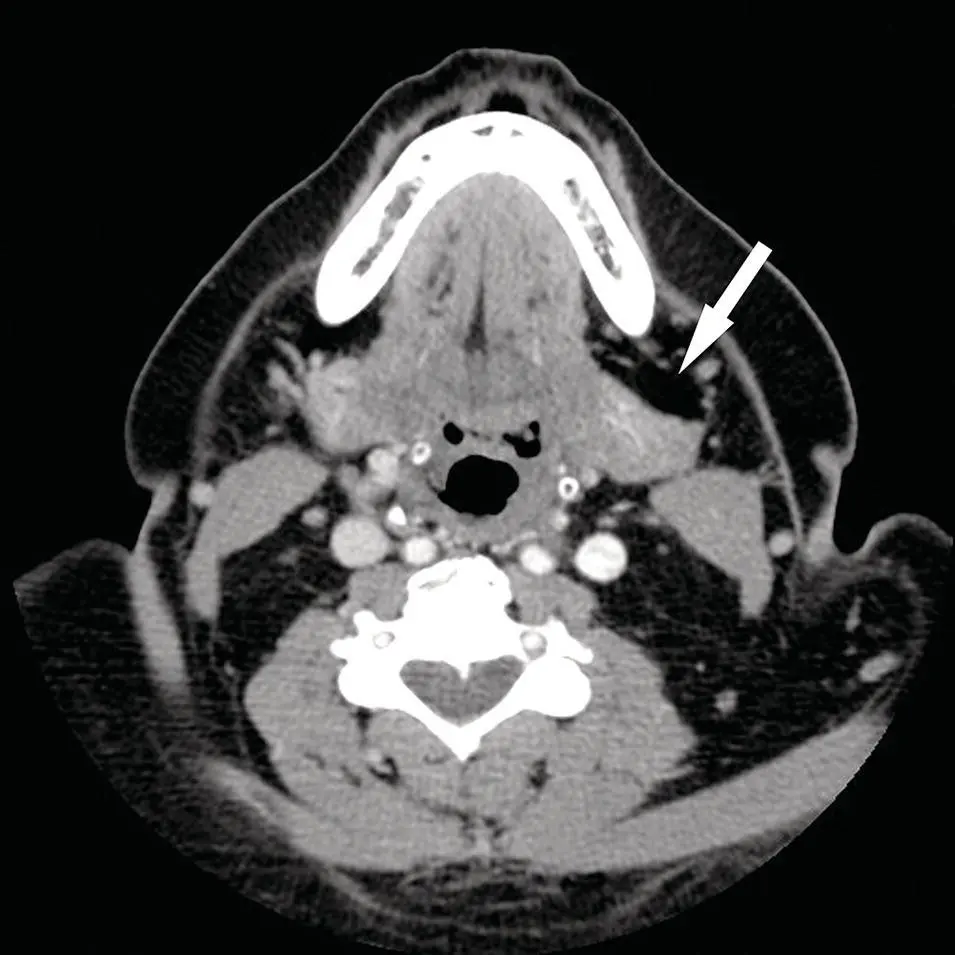

Figure 2.3. Axial CT of the skull base reconstructed in a sharp algorithm and in bone window and level display demonstrating sharp bone detail. Note the sharply defined normal right stylomastoid foramen (arrow).